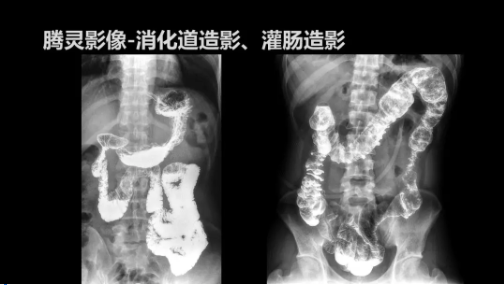

“騰靈”是安健科技的第四代動(dòng)態(tài)DR產(chǎn)品,可實(shí)現(xiàn)全科室應(yīng)用。如各類常規(guī)的X線檢查、消化道檢查、骨科檢查、婦科、兒科檢查等。此外,安健科技為“騰靈”在真正意義上實(shí)現(xiàn)多科室、多功能診斷進(jìn)行了多項(xiàng)針對(duì)性設(shè)計(jì)。

相較前代產(chǎn)品,“騰靈”在圖像質(zhì)量方面得到了全面升級(jí),“騰靈”采用17*17非晶硅平板探測(cè)器設(shè)計(jì),采集矩陣達(dá)3072*3072,動(dòng)態(tài)范圍達(dá)16bit,為成像提供超大視野的同時(shí)保證成像質(zhì)量,此外,該款機(jī)型可根據(jù)醫(yī)療機(jī)構(gòu)的差異化需求而選配不同的動(dòng)態(tài)平板探測(cè)器,以此來(lái)適應(yīng)不同階層用戶所需。

此外,“騰靈”為了能夠幫助醫(yī)生更快速、有效的定位病灶,還增加了多項(xiàng)精準(zhǔn)診斷保障功能,如支持動(dòng)態(tài)觀察診斷,實(shí)時(shí)高清點(diǎn)片等。“騰靈”透視切換高清點(diǎn)片曝光,捕捉關(guān)鍵病灶診斷僅需0.8s,同時(shí)還支持圖像局部放大,醫(yī)生可自由切換15’12’和9’三種放大模式,另外,“騰靈”還支持視頻保存、回放功能,幫助醫(yī)生在檢查結(jié)束后通過(guò)回放查看細(xì)節(jié),為醫(yī)生的診斷增加信心。